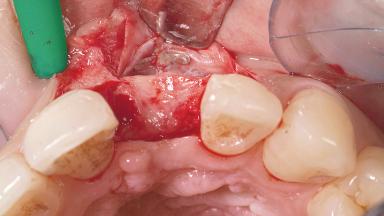

Bone Augmentation Horizontal|Staged

Augmentation Materials Autogenous chips|Membrane

Bone Volume Deficient horizontally, requiring prior grafting